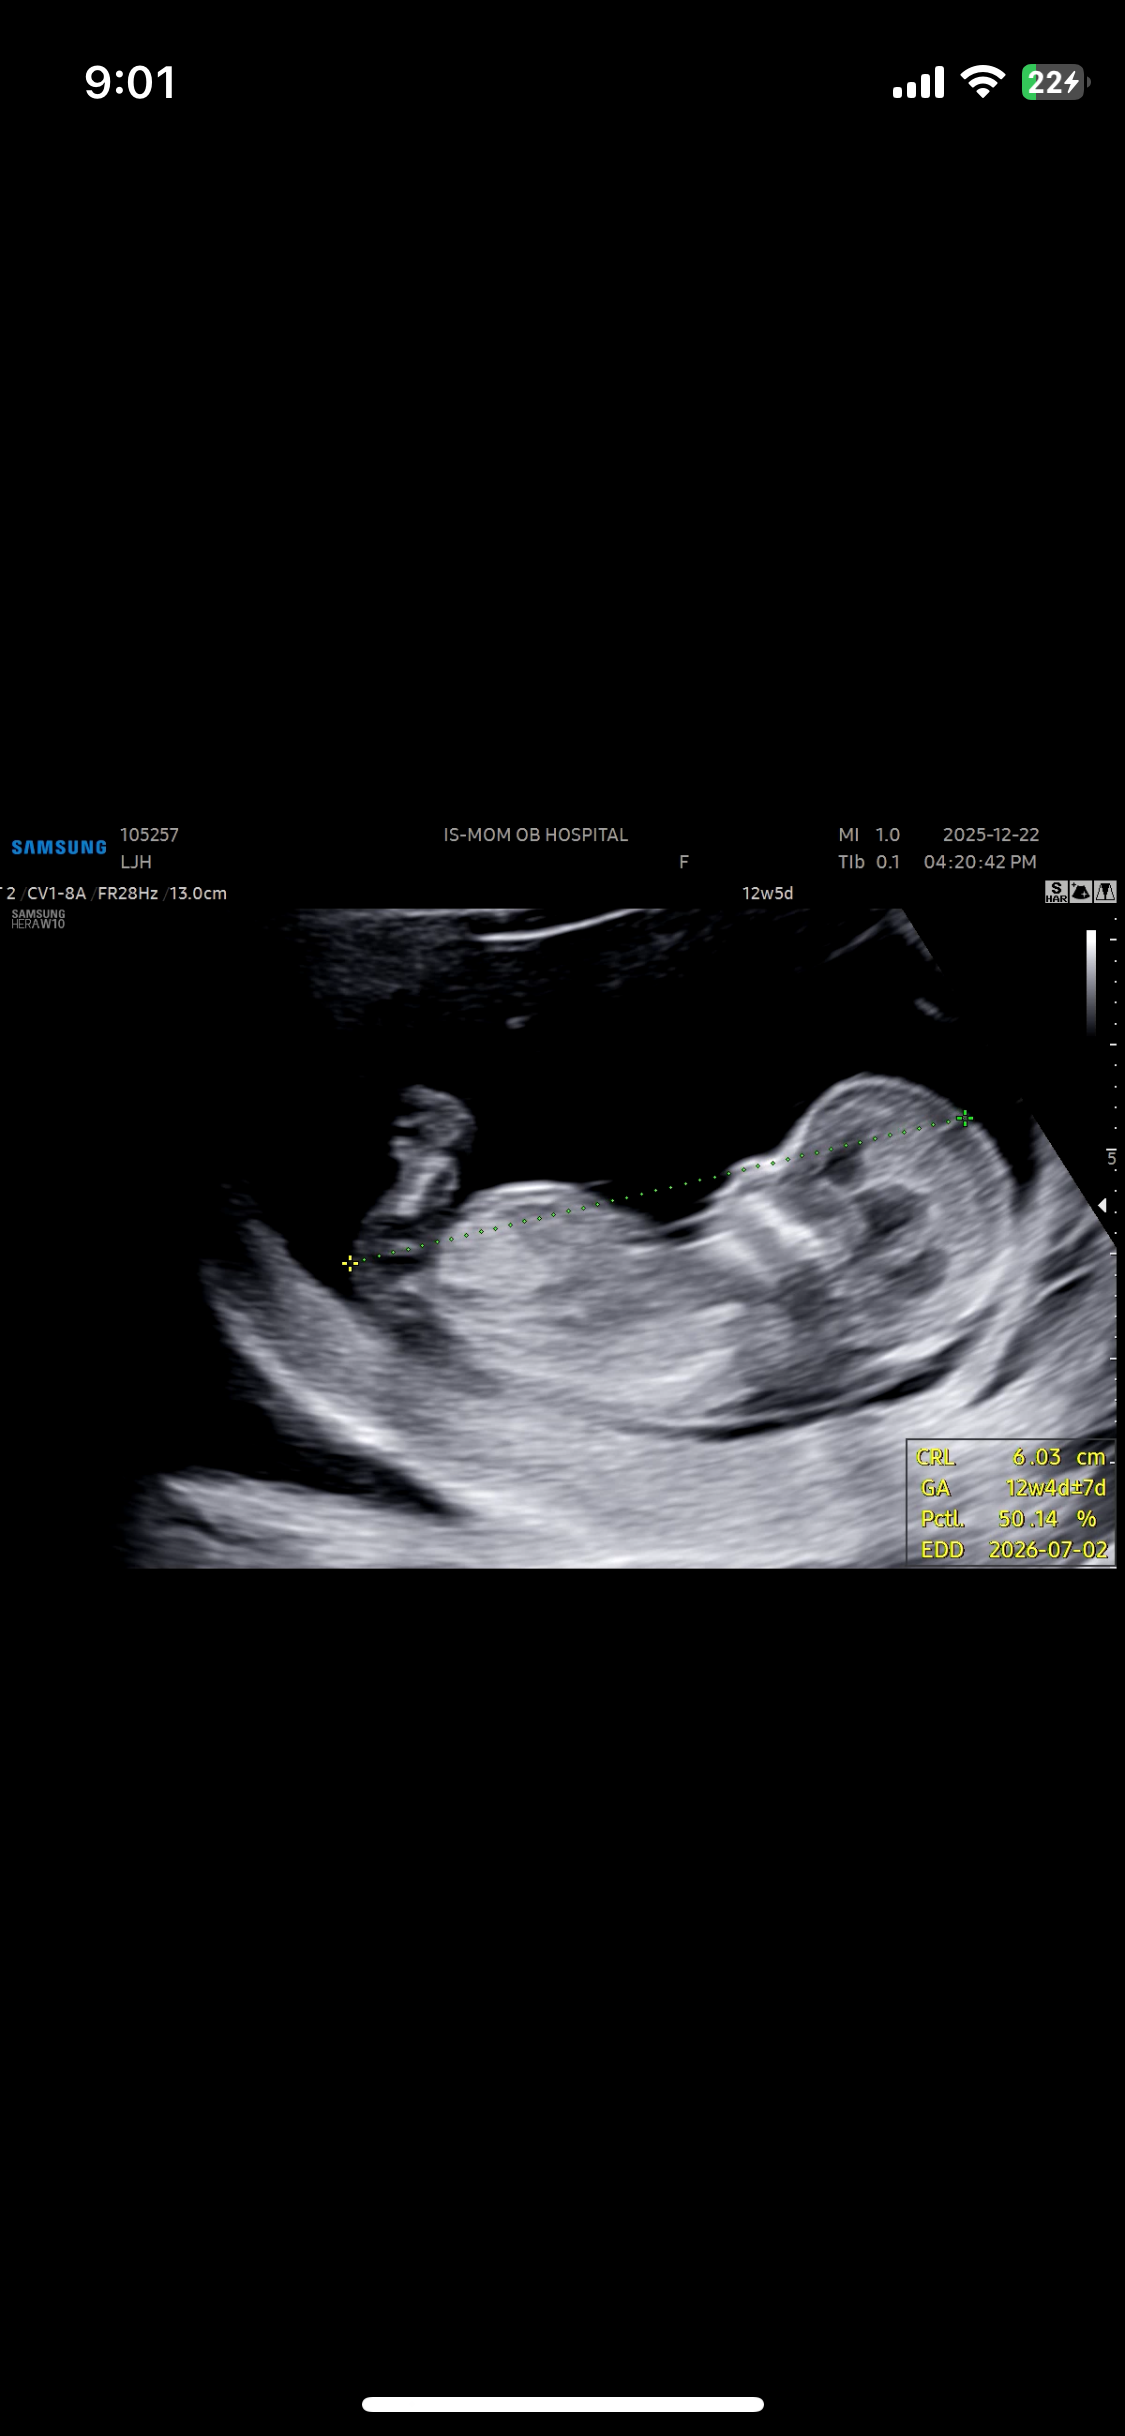

각도법 보는법? 아들같나여?

다들 각도법 어쩜 그리 잘보시는지...전 어디가 성기인지모르겠어요 ㅜ 근데 아들 같은 이느낌... 어때보이세요?